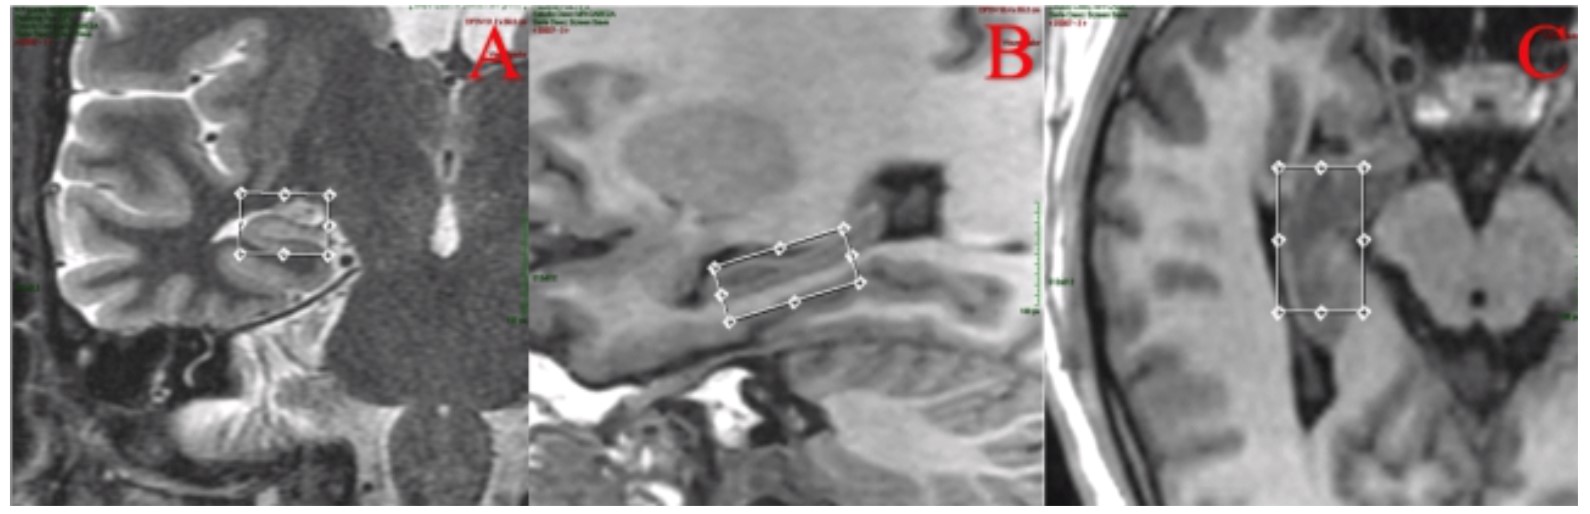

La espectroscopia es una técnica utilizada en equipos de alto teslaje que se obtiene con técnica uni voxel, con tamaño del voxel de 10 x 10 x 25, 2500 mm. posicionado sobre el lóbulo mesotemporal incluyendo en hipocampo (Figura 5)(42). En esclerosis mesial temporal demuestra disminución del pico del NAA (N-Acetil Aspartato) y de los ratios NAA/Cho (Colina), NAA/Cr (Creatina) y NAA/ Cho-Cr en el lado patológico hasta en el 90 % de los casos indican pérdida neuronal y disfunción. Sin embargo, este hallazgo también lo podemos observar en el lado contralateral en un 30 % - 40 %. La relación NAA/colina+creatinina es el parámetro más sensible para detectar la anormalidad funcional en el hipocampo afectado. Una reducción de este índice menor a 0.71 ppm(Figura 6)(43 -47) y un índice de asimetría menor del 11 % es patológico, lo que permite identificar la lateralización. Si la relación NAA/Colina +Creatina está afectada en los dos hipocampos el índice utilizado para lateralización es de 5.5 % (43,44).

La tractografía puede demostrar reorganización estructural de los tractos asociados a memoria y lenguaje de acuerdo con la localización de la lesión y a la dominancia hemisférica; en pacientes con dominancia hemisférica izquierda y esclerosis temporal mesial ipsilateral se ha demostrado aumento de los tractos de sustancia blanca del hemisferio contralateral como resultado de reorganización funcional del lenguaje en regiones corticales contralaterales (61,62). La evaluación del fascículo arcuato que conecta las áreas receptivas y productivas del lenguaje ha demostrado ser mayor en el hemisferio dominante y esa asimetría se reduce cuando existe lesión en el hemisferio dominante secundaria a reorganización funcional (63,64), mientras que la evaluación del fascículo uncinado (Figura 7) y los datos de reorganización neuronal permiten predecir el desarrollo de afasia (65).